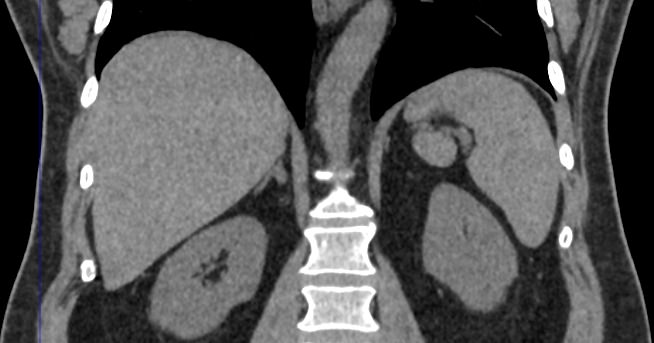

Одним из наиболее информативных методов диагностики заболеваний надпочечников является мультиспиральная компьютерная томография. МСКТ надпочечников относится к лучевым методам исследования, то есть для получения послойного изображения структуры органа используется проникающая способность рентгеновских лучей.

В клинике «Доступная медицина» мультиспиральная КТ надпочечников выполняется на современном 128-срезовом томографе экспертного класса TOSHIBA AQUILION CXL, который производит множество послойных снимков за несколько секунд. Быстрота исследования обеспечивает пониженный уровень лучевой нагрузки на пациента, а благодаря инновационным компьютерным программам томограф создает трехмерные модели органа, позволяющие оценить структуру надпочечников и окружающие ткани.

Кроме нативной компьютерной томографии МСКТ надпочечников проводится с применением рентгеноконтрастного вещества на основе йода. Контраст вводится пациенту внутривенно и усиливает визуализацию новообразований на фоне неизмененных тканей.

Контрастирование позволяет, в первую очередь, обнаружить опухоли минимальных размеров, что особенно важно при онкологических процессах для назначения своевременного лечения.